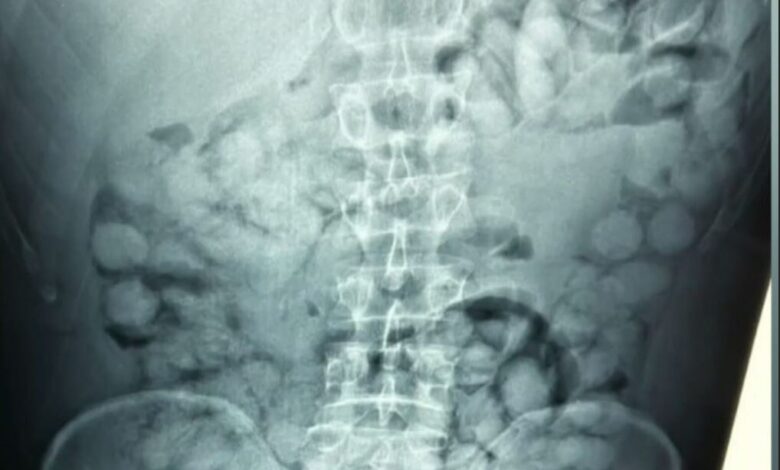

Şahsın Sao Paulo’dan yola çıkarak Fransa aktarmalı geldiği tespit edilirken, yapılan detaylı arama sonucunda şüphelinin midesinde çok sayıda yabancı madde olduğu anlaşıldı. Hastaneye sevk edilen zanlının çekilen röntgeninde, midesinde adeta “yumurtaya” benzeyen 100 adet kapsül olduğu ortaya çıktı.

Yunan polisi tarafından paylaşılan görüntülerde, şahsın midesindeki kapsüller net bir şekilde görülüyor. Her biri 11 gram ağırlığındaki toplam 100 kapsülün içinde kokain olduğu tespit edildi. Toplam kokain miktarının 1 kilogramdan fazla olduğu belirtildi.